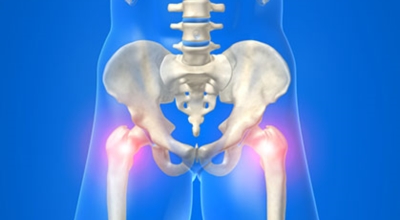

고관절염은 고관절에 발생하는 관절염을 말하며 고관절의 연골이 닳게 되면서 뼈와 뼈가 서로 부딪히며 통증을 유발하게 됩니다. 고관절염 초기 증상으로는 사타구니 부위가 불편하게 느껴지며, 무리하면 통증이 발생할 수 있고 관절염 증상이 악화되면서 사타구니에서 느끼던 통증이 허벅지와 엉덩이 통증으로 이어지기도 하는데요 고관절염 통증 증상으로 초기에는 허리 통증이 나타나 허리 질환과 혼동하기 쉬우며 특히 척추질환이 있는 사람은 고관절 통증 증상과 마찬가지로 엉덩이, 다리 통증이 동반되기 때문에 더욱 헷갈리는 경우가 많다고 합니다.

또한 고관절이 있는 부위는 근육과 지방으로 덮여 통증을 제대로 감지하기 어려워 고관절 통증 증상으로 인한 질환을 발견하기 쉽지 않은 경향이 있습니다. 따라서 평소에 사타구니 통증이 지속되거나 특히 양반다리를 할 때 통증이 있다면 고관절 질환을 의심해볼 수 있으며 격렬한 운동을 즐겨하는 사람이나 체중이 많이 나가는 사람들에게는 퇴행성 고관절염이 생길 가능성이 있으므로, 이러한 경우 허리 통증이 느껴지면 퇴행성 고관절염을 의심해보고 적절한 검진을 받아보는 것이 좋습니다.